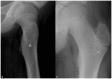

Less than 10% of chondrosarcomas occur in children. In addition, as little as 0.5% of low-grade chondrosarcomas arise secondarily from benign chondroid lesions. The presence of focal pain is often used to crudely distinguish a chondrosarcoma (which is usually managed with wide surgical excision), from a benign chondroid lesion (which can be followed by clinical exams and imaging surveillance). Given the difficulty of localizing pain in the pediatric population, initial radiology findings and short-interval follow-up, both imaging and clinical, are critical to accurately differentiate a chondrosarcoma from a benign chondroid lesion. To our knowledge, no case in the literature discusses a chondrosarcoma possibly arising secondarily from an enchondroma in a pediatric patient. We present a clinicopathologic and radiology review of conventional chondrosarcomas. We also attempt to further the understanding of how to manage a chondroid lesion in the pediatric patient with only vague or bilateral complaints of pain.